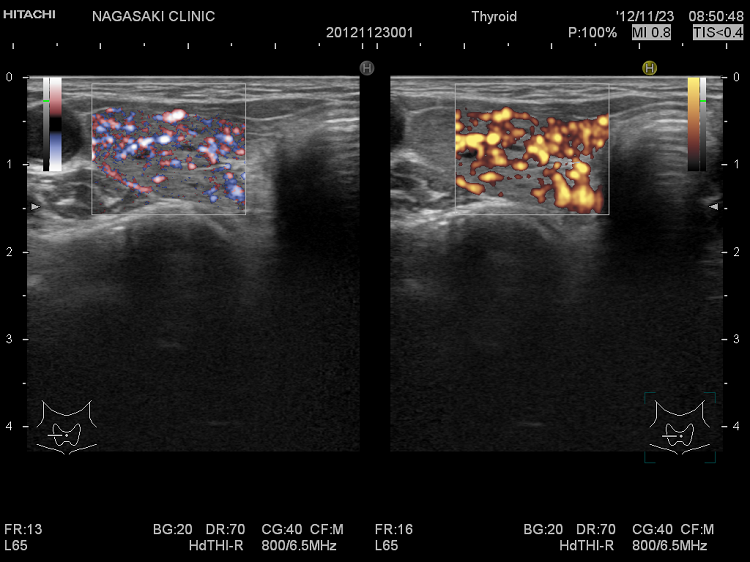

局所的に血流が多く、低エコーな領域

抗甲状腺薬投与により、甲状腺機能が正常に保たれているバセドウ病では、治療前の”火炎状血流増加”と呼ばれる甲状腺内部の異常血流増加が減少していきます。しかし、局所的に血流が多く、低エコーな領域は活動性が残存しています。(J Clin Ultrasound. 2005 Oct;33(8):381-5. doi: 10.1002/jcu.20157.)(Exp Clin Endocrinol Diabetes. 2013 Jan;121(1):1-5.)(AJR Am J Roentgenol. 1996 Jan;166(1):203-7.)

局所的に血流が多く、低エコーでバセドウ病の活動性が高い領域

局所的に血流が多く、低エコーでバセドウ病の活動性が高い領域  ドプラーモード

バセドウ病 局所的に活動性が高い部位

バセドウ病 局所的に活動性が高い部位(低エコー)

バセドウ病 局所的に活動性が高い部位 ドプラーモード

バセドウ病 局所的に活動性が高い部位 ドプラーモード(低エコー領域は局所的に血流が多く)